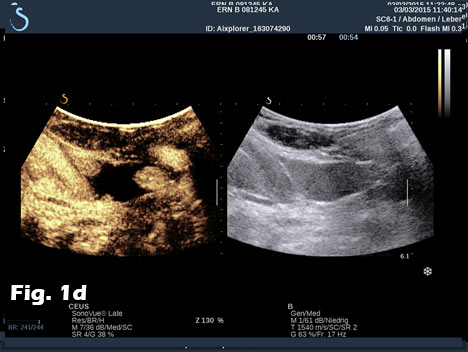

We report on the incidental finding of a 70 y/o patient presenting with an indolent cervical swelling and mass. Clinical examination and laboratory data were not conclusive. In the figure sequence B mode ultrasound and shear wave elastography revealed a 43 mm mass lesion with peripherally stiffer tissue (a) with thrombosis in statu nascendi of jugular vein shown by B mode (b) and also by contrast enhanced ultrasound (c) and shear wave elastography (d). 3D shear wave elastography confirmed the circumscript peripherally stiffer cervical mass (e). 3D SWE added complementary information for a better delineation of the distribution of increased stiffness, following the fibrous capsule around the nerve. SWE also showed feasibility to demonstrate stiffer tissue within jugular vein. 3D techniques allowed improved documentation of the anatomical volume including the tumour and surrounding vessels [(1-3)]. Histologically the nerve tumour schwannoma was proven.

Figure 1:B mode ultrasound and shear wave elastography revealed a 43 mm mass lesion with peripherally stiffer tissue (a) with thrombosis in statu nascendi of jugular vein (b), also shown by contrast enhanced ultrasound (c) and shear wave elastography (d). 3D shear wave elastography confirmed the circumscript peripherally stiffer cervical mass (e).